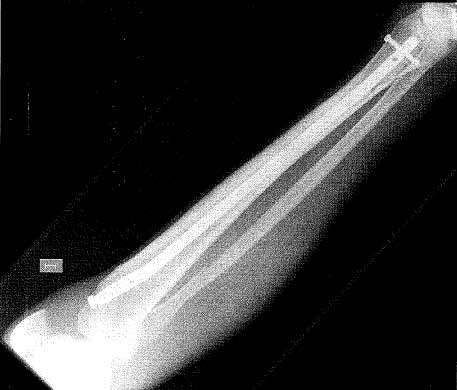

temporada una rotura de tibia y peroné. “Fue por una mala caída cuando otro

jugador chocó contra mí para quitarme el balón, se me quedó el tobillo

bloqueado y por eso me partí el hueso”, ha declarado Javier. Antes de

producirse la fractura, López Cilla había sufrido la rotura del ligamento

cruzado de la rodilla de la misma pierna.

| Radiografía de la pierna de Javier Lopez Cilla con el clavo de titanio, después de la operación. Foto: Javier López Cilla. |

En el caso de López Cilla, Cuervas Mons, tuvo que realizar

una intervención quirúrgica por la cual “el paciente lleva introducido dentro

del hueso de la tibia un clavo de titanio de 40 centímetros, y cuando el hueso

esté completamente recuperado, se procederá a su extracción”. El traumatólogo